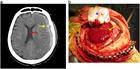

急性硬膜下血腫

1. 頭部外傷受傷直後から片麻痺等の神経症状や意識障害が持続する場合には、急性硬膜下血腫の存在を想起し呼吸・循環管理を行いつつ速やかに頭部CT撮影を行い診断する。

1. 抗血栓薬内服中の高齢者では軽微な外傷でも受傷することがあり、急速な意識障害の進行や亜急性の経過をとることもあり注意を要する。